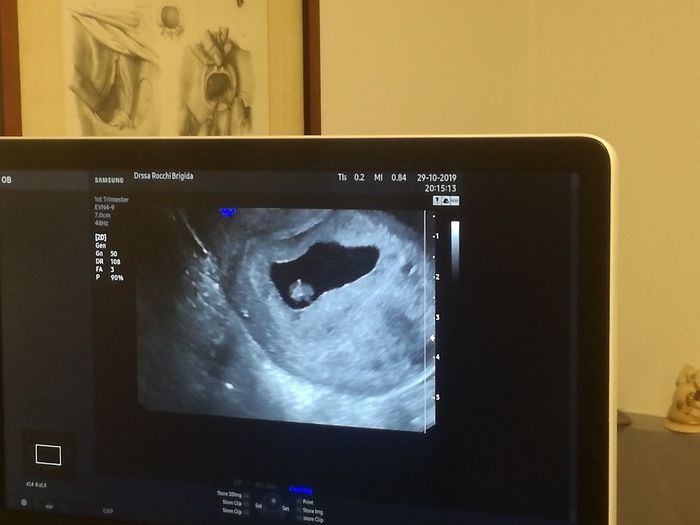

La prima visita risale a due settimane fa..ero di 6 settimane e fortunatamente sono riuscita a vedere il cuoricino che batteva...adesso non ho quasi più nessun sintomo..e la prossima visita sarà giovedì...ho una paura assurda di scoprire che nn c'è...